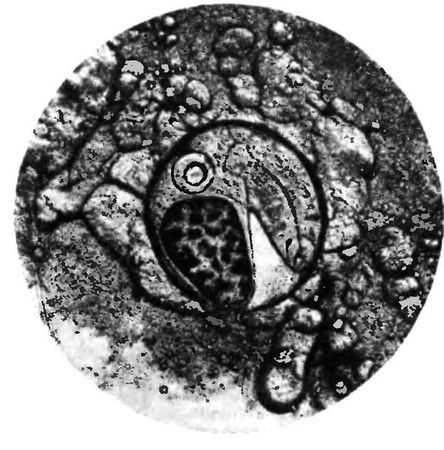

В организме водных моллюсков (Bithynia), проглотивших яйца, развиваются личинки – церкарии. Развитие их продолжается менее 2 мес. Затем церкарии выходят в воду, активно проникают в тело карповых рыб (язь, елец, плотва и др.), где в мышцах превращаются в следующую, инвазионную (заразную) личинку – метацеркарий, покрытую оболочкой (рис. 4.5). У метацеркариев сибирского сосальщика на тонком переднем конце видны шипики, а также крупные экскреторный пузырь черного цвета, овальный или слегка лопастной, ротовая и брюшная присоски, петли кишечника. Размер личинок 0,23–0,37 мм.

Метацеркарии становятся инвазионными для человека уже через 6 дней. Человек заражается при употреблении в пищу слабо провяленной, малосольной, подвергнутой недостаточной термической обработке или сырой (строганина) рыбы. В кишечнике человека личинки освобождаются от оболочек, проникают через общий желчный и панкреатический протоки в печень, желчный пузырь и поджелудочную железу. Через месяц паразиты достигают половой зрелости и начинают выделять яйца. В организме человека кошачий (сибирский) сосальщик может паразитировать много лет.